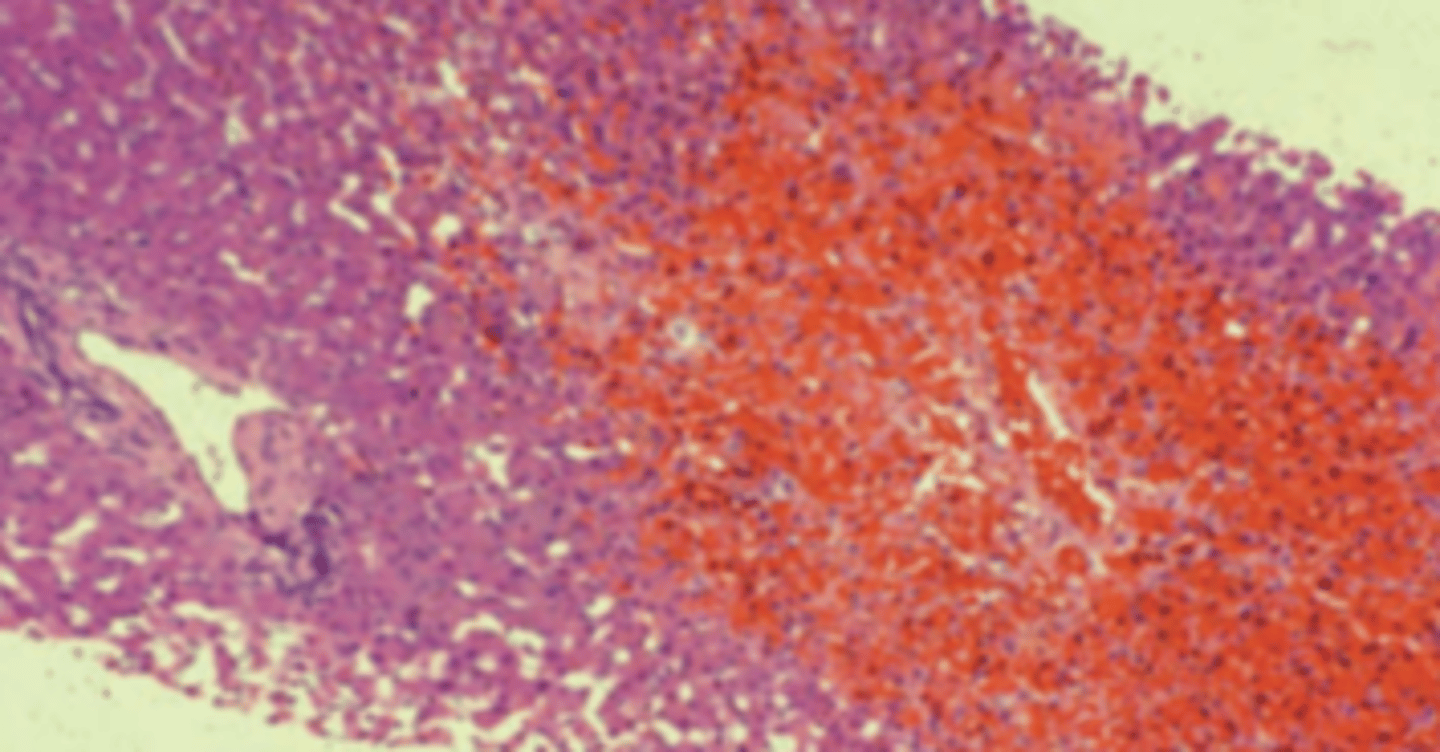

Budd-Chiari syndrome

A 28-year-old woman presents with a 4-day history of abdominal pain and increasing abdominal girth. She does not drink alcoholic beverages but smokes a pack of cigarettes a day. Except for oral contraceptives, she takes no medications. Physical examination shows hepatomegaly, ascites, and mild jaundice. A liver biopsy is obtained (shown in the image). Which of the following is the most likely diagnosis?

(A) Budd-Chiari syndrome

(B) Chronic hepatitis B

(C) Extrahepatic cholestasis

(D) Primary biliary cirrhosis

(E) Secondary biliary cirrhosis